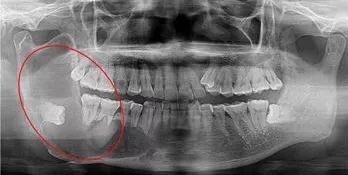

阻生牙(impacted teeth)是指部分萌出或完全不能萌出,且以后也不会自行萌出的牙。好发部位为下颌第三磨牙、上颌第三磨牙及上颌尖牙,其中阻生第三磨牙也叫做阻生智齿。

7、智齿周围囊性病变:下颌阻生的智齿常常形成囊肿,引起骨头吸收。